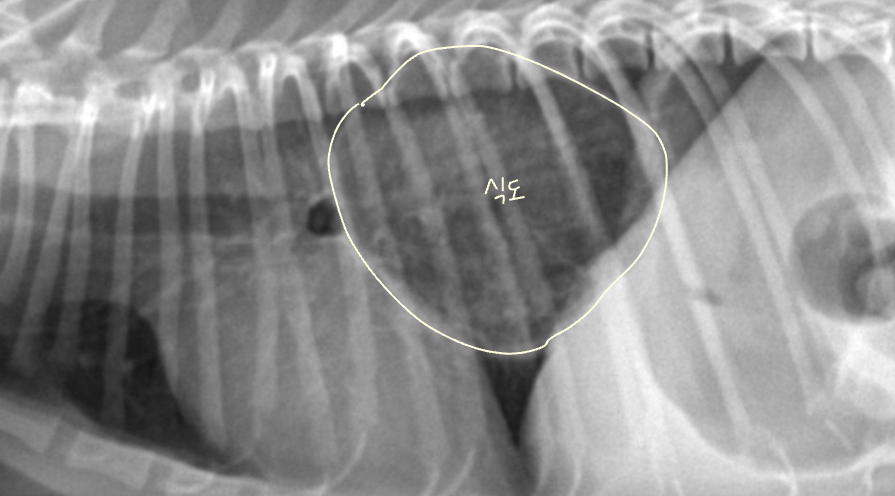

1. Esophagus (์๋)

- ์๋ : ์ฐ๋ถ์กฐ์ง, ํก๊ฒฉ๋ง์ ๊ฑฐ์ณ ํ๋ง์ ๋ซ๊ณ ์๋ก ๋ค์ด๊ฐ.

- ์ ์์ ์ผ๋ก๋ ๊ณต๊ธฐ๊ฐ ์์ด collapsed. gas๊ฐ ์ฐจ๋ฉด ๋ณด์ผ ์ ์์.

- ์ ์ ์๊ฒฌ

- ๋ง์ทจ๋ ํฅ๋ถ์ ์ํด ์ ์์ ์ผ๋ก ์๋๋ด ๊ฐ์ค๊ฐ ๋ถ๋ถ์ ์ผ๋ก ์ถ์ ๋ ์ ์์.

- ํ๊ฐ ์ ๊ตฌ๋ถ ์๋์ ๋ฏธ์ฝํ ํ์ฅ๊ณผ ์๋ ์ฃผํ์ ๋ณํ์ ์ ์.

์๋์ ๋ณ์ ์๊ฒฌ

- ์ด๋ฌผ, ์๋ํ์ฅ์ฆ, ์ผ์ฆ, ์๋ํ์ฐฉ์ฆ, ์๋์์ค์ฒฉ, ์ข ์(rare)

- ๋ฐฉ์ฌ์ ์ ์๊ฒฌ : ์๋๋ด ๋ฐฉ์ฌ์ ๋ถํฌ๊ณผ์ฑ, ๊ฐ์ค ์ถ์ , ํ์ฅ๋ ์๋ฒฝ

- ์ง๋จ : ์กฐ์ ํฌ์๋ฐฉ์ฌ์ , CT, ์ด์ํ, ๋ด์๊ฒฝ

Tracheoesophageal strip sign (์๋ ๋ด ๊ฐ์ค ์ถ์ )

- Tracheoesophageal strip sign : ์๋ ํ์ฅ์ ์ํด ๊ธฐ๊ด๊ณผ ์๋๊ฐ ๊ฒน์ณ ๋ํ๋๋ ๊ฐ๋๊ณ ํํํ ๊ณต๊ธฐ ์์.

- ์๋์ ๊ฐ์ค ์ถ์ ๋์ด ์๋ค๋ฉด

- ํฅ๋ถ์ด๋ ๋ง์ทจ๋ก ์ธํ ์ผ์์ ์ถ์ (์ ์)

- ์ด๋ฌผ๋ก ์ธํ ๋งํ

- MG์ ์ํ ์๋ํ์ฅ์ฆ (์๋๊ทผ ๋ฌด๋ ฅํ)